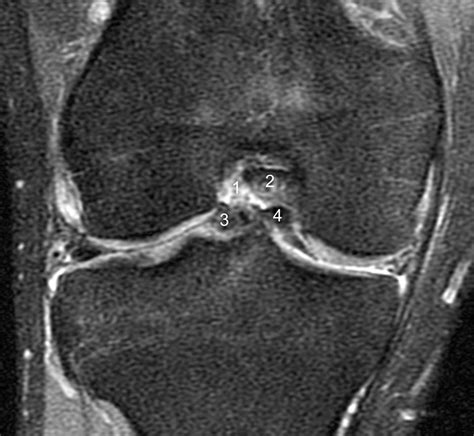

A Bucket Handle Meniscus Tear is a specific type of meniscus tear where a longitudinal tear occurs, causing a portion of the meniscus to displace and flip into the joint space. This displacement can resemble the handle of a bucket, hence the name. This type of tear is often more severe than other types of meniscus tears and can lead to significant knee instability and pain.

• Imaging Tests: Magnetic Resonance Imaging (MRI) is the gold standard for diagnosing meniscus tears. It provides detailed images of the knee joint, allowing for accurate identification of the tear.